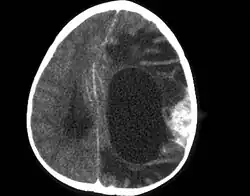

Ustalono kryteria kliniczno-patologiczne rozpoznania DIG/DCAI[5]:

- Występowanie w okresie niemowlęcym

- Nadnamiotowe umiejscowienie z zajęciem powierzchownych warstw kory mózgowej

- Duży rozmiar guza połączony z obrazem torbieli

- Gęste podścielisko z desmoplazją i tworzenie błon podstawnych.